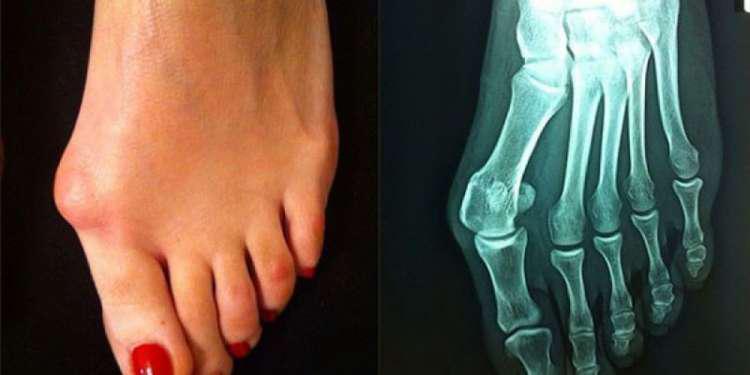

«Τσιμπημένο» αλάτι, κουρασμένα οστά…